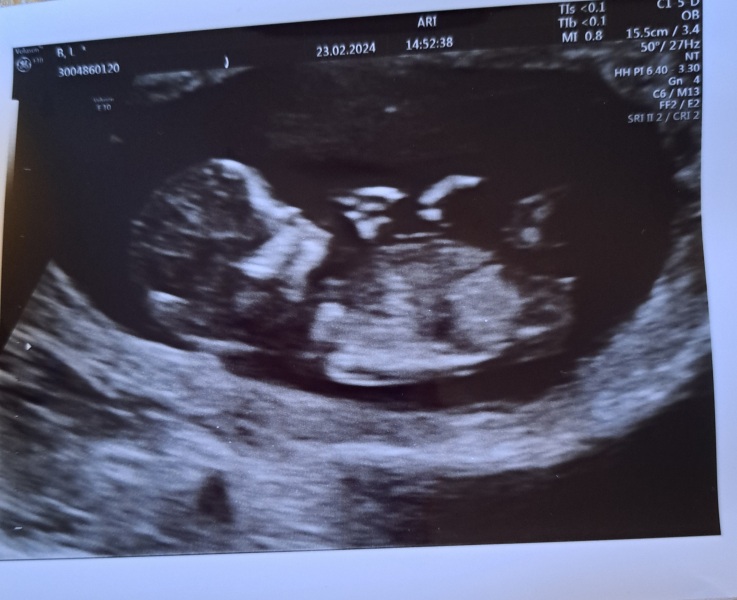

All good at the scan 😃

I was put a few days ahead so will be 13 weeks on Sunday. Due date 1st Sept 🥳

They were really moving around which made it difficult to get measurements. Can't believe I can't feel all that dancing. I wasn't charged for my scans and was given 6. They are doing a weird little hand dance in this one.